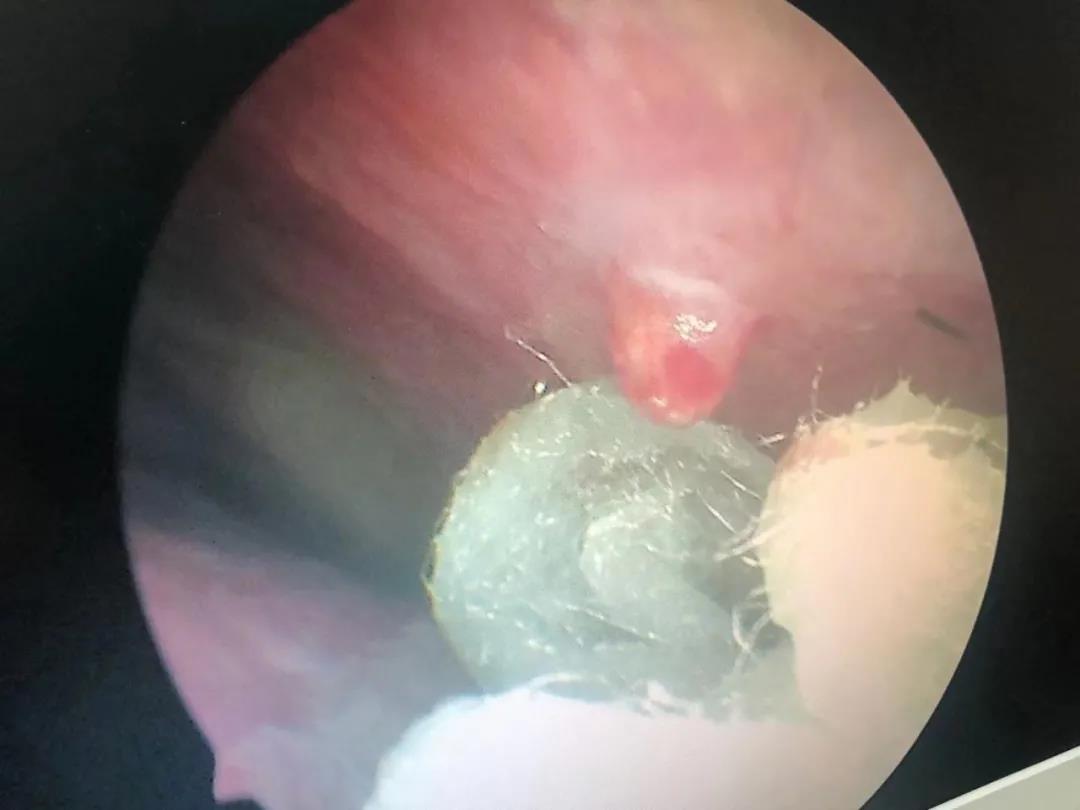

“你這個(gè)不是鼻中隔偏曲啊,是血管瘤造成的,你看這里有一個(gè)血管瘤”。耳鼻喉科專家黃定強(qiáng)博士通過鼻內(nèi)鏡檢查發(fā)現(xiàn),吳大叔鼻腔內(nèi)有一顆約黃豆大小的血管瘤。

(吳大叔鼻內(nèi)鏡下血管瘤)

像吳大叔的情況,就是非常明確的鼻部毛細(xì)血管瘤。之后黃博士為吳大叔進(jìn)行了局麻下鼻腔毛細(xì)血管瘤切除術(shù)。